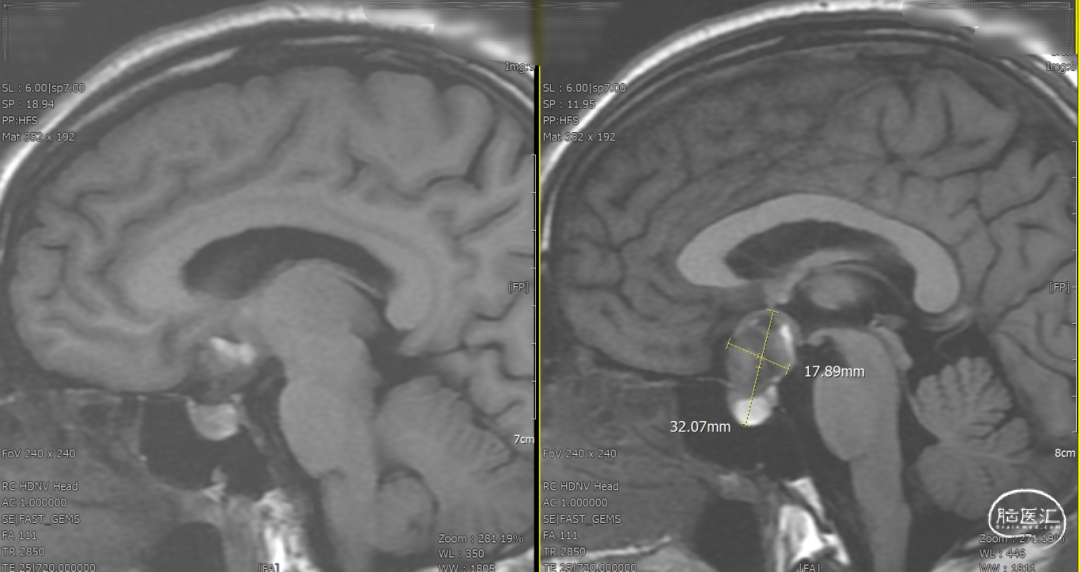

DSA造影3D重建测量

2.5mm*15mm Surpass Evolve密网支架,支架锚定区为右侧A2~A1

术后一天检查。